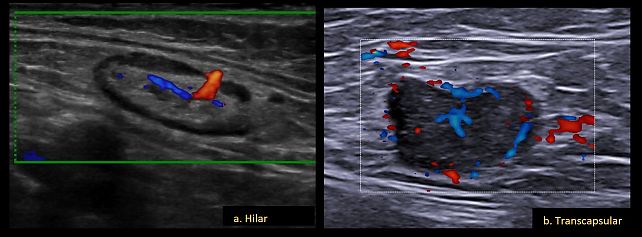

Vascular criteria

Using Doppler (color or power), with pulse repetition frequency (PRF) set at 0.3–0.6 kHz and with minimal probe pressure, the vascularization score (1–4) is assigned as per IOTA guidelines.22 Blood vessel architecture is described as: hilar (central, parallel to long axis) (Figure 11a), transcapsular (vessels penetrating from the outside) (Figure 11b) or combined (both patterns).

11

Lymph node blood-vessel architecture, showing hilar (a) and transcapsular (b) patterns.